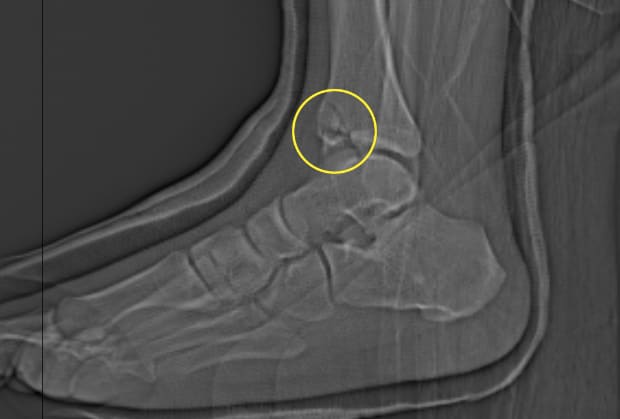

Hey Y'all!!!! So.....I'm recovering from breaking my Left Tibia right above the ankle joint playing soccer my second passion behind golf...Hoping for a good few weeks...I'm already in a cast and getting a CT scan soon to make sure everything looks good...I have the second opinion Doctor lined up if necessary. We just moved back to Carlsbad and this setback has me Really bummed out about not being able to golf with my family and friends....Arrghhh!!! Staying positive I'll be back out on the practice green chipping and putting by late September.

Well...No Surgery at the moment...basically there is no solid bone to put screws and plates into to stabilize the break. The front of the Tibia looks like broken potato chips. I'll be in a cast and monitored bi weekly during the healing process.